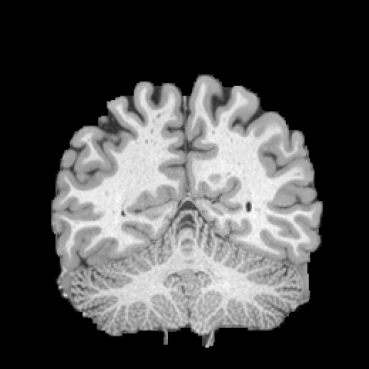

Inverse consistent rigid, affine, nonparametric, and MLP registration. We train networks on MNIST 5s using the methods in Secs. 3 and 4, demonstrating that the resulting networks are inverse-consistent. Our TwoStepConsistent (TSC) operator can be used on any combination of the networks defined in Sec. 3. For demonstrations, we join an MLP registration network to a vector field registration network, and join two affine networks to two vector field networks. Fig. 2 shows successful inverse-consistent sample registrations.

| Moving Image | Warped Image | Fixed Image | Moving Image | Warped Image | Fixed Image |